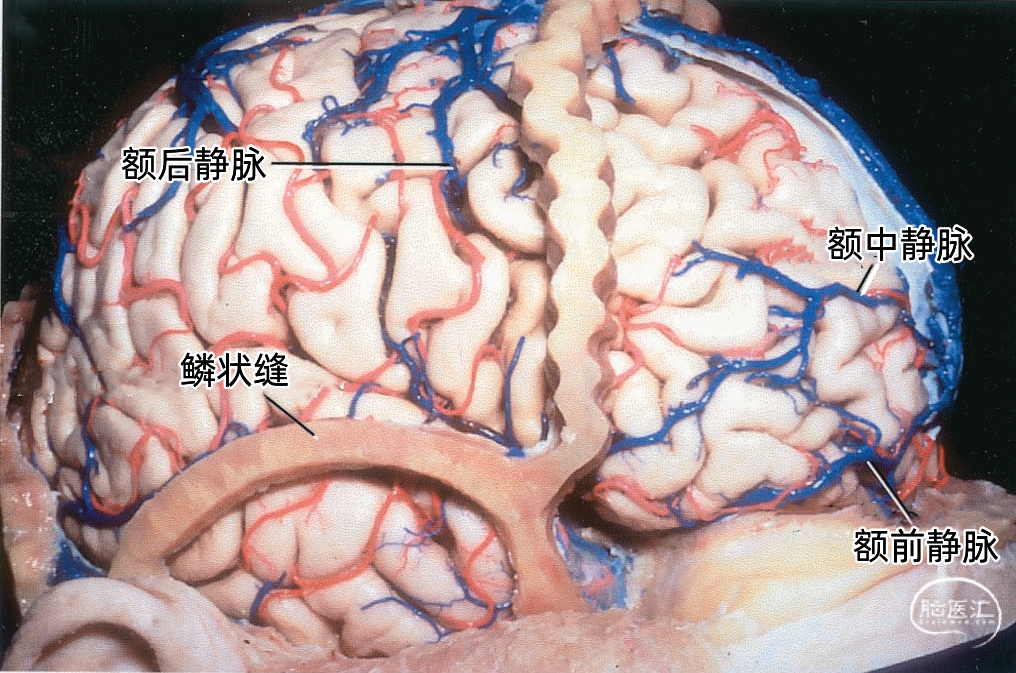

从两侧皮层汇入上矢状窦的皮层静脉具有特有的形态(下图)。左侧显示汇入上矢状窦的静脉,右侧显示静脉入窦的平均角度。从前到后,静脉入窦的角度逐渐减小。 额极附近的静脉,与上矢状窦内血流方向一致,汇入上矢状窦; 额叶后部的静脉向前汇入上矢状窦,与窦内血流的方向相反; 顶叶和枕叶的静脉向前汇入上矢状窦,与窦内血流方向相反;| 额极静脉 110° | 额前静脉 110° |

| 额中静脉 85° | 额后静脉 65° |

| 中央前静脉 50° | 中央静脉 45° |

| 中央后静脉 40° | 顶前静脉 25° |

| 顶后静脉 15° | 枕静脉10° |

下图示右侧额中静脉、额后静脉先进入靠近上矢状窦的硬膜窦。然后再进入矢状窦。额前静脉直接引流入上矢状窦。黄色箭头所指为硬膜窦,右侧有2个,左侧有3个。